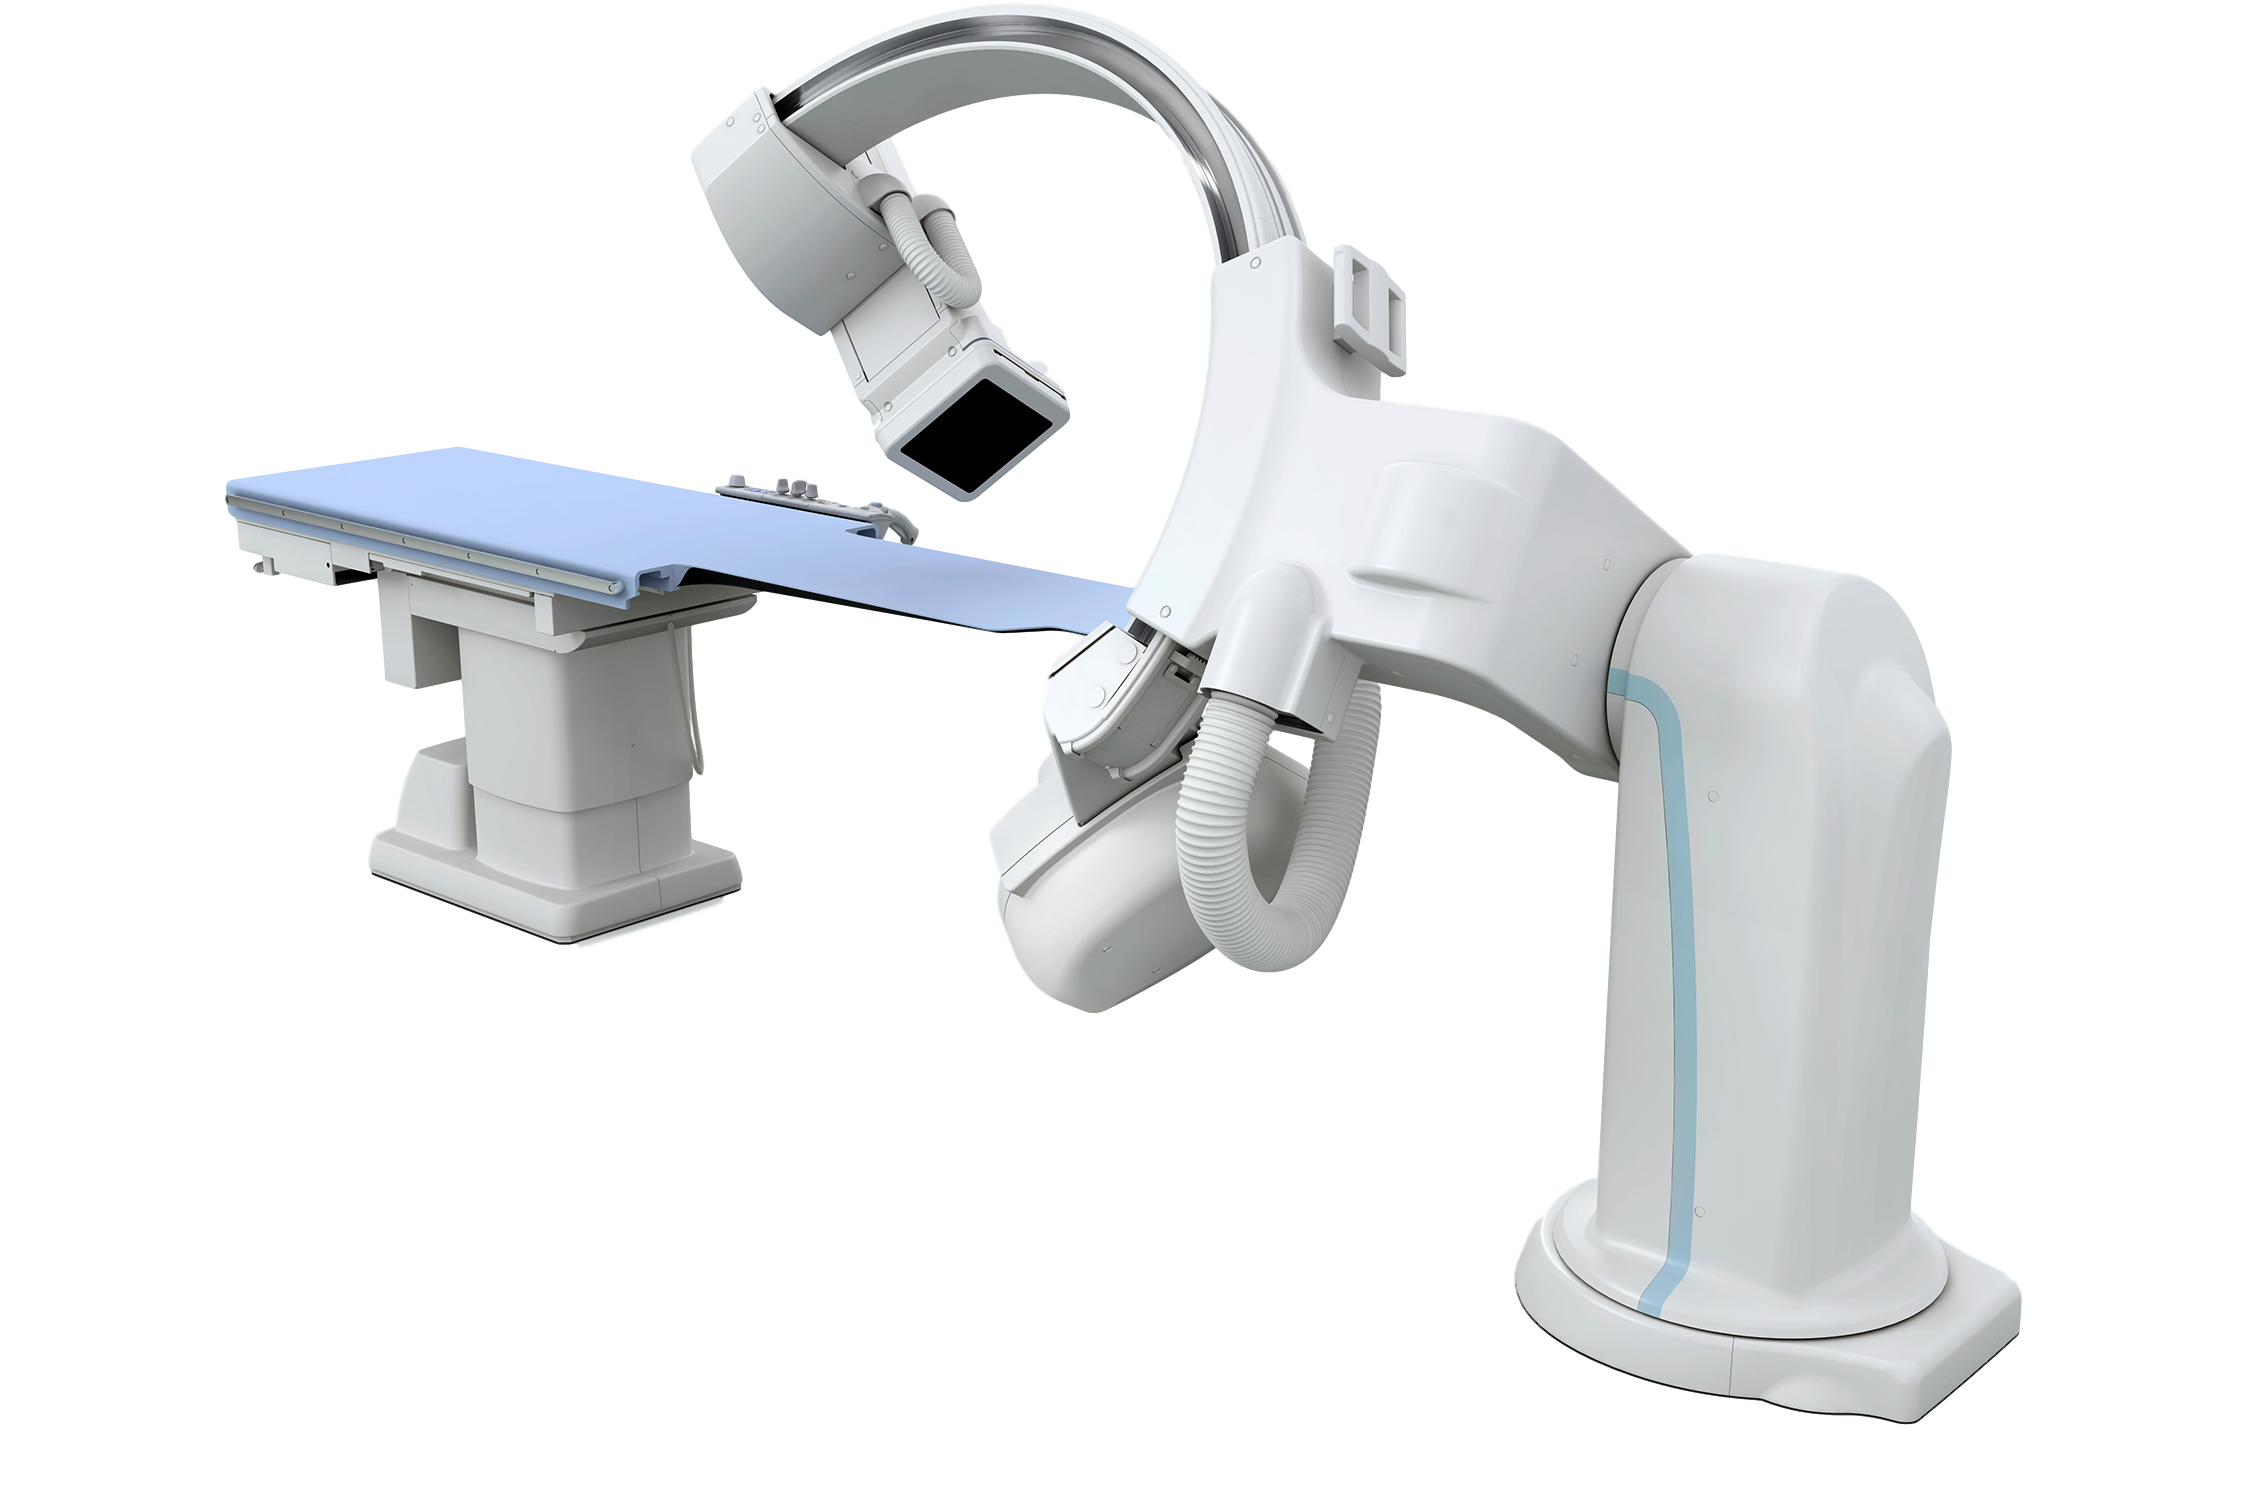

Одно из преимуществ ангиографа СF-I/SP серии Infinix-i - это простота использования. Упрaвление интуитивно, что снижaет потребность в помощи лаборантов. Перед началом исследования можно быстро получить доступ к информации о пациенте и предыдущих исследованиях для повышения эффективности исследований.

Возможности оператора:

- управление движением С-арки и стола для исследования сосудов;

- контроль размера поля зрения;

- установка рентгеновского коллиматора и данных автопозиционирования;

- выбор режима рентгеноскопии;

- установка других параметров, необходимых для исследования.

Характеристики многоосевой однопроекционная система напольного крепления:

- Подвижная С-арка, которая обеспечивает быстрое позиционирование и широкий доступ к пациенту

- Тип стационарный моноплановый

- Крепление С-дуги напольное

- Глубина C-дуги 89 см